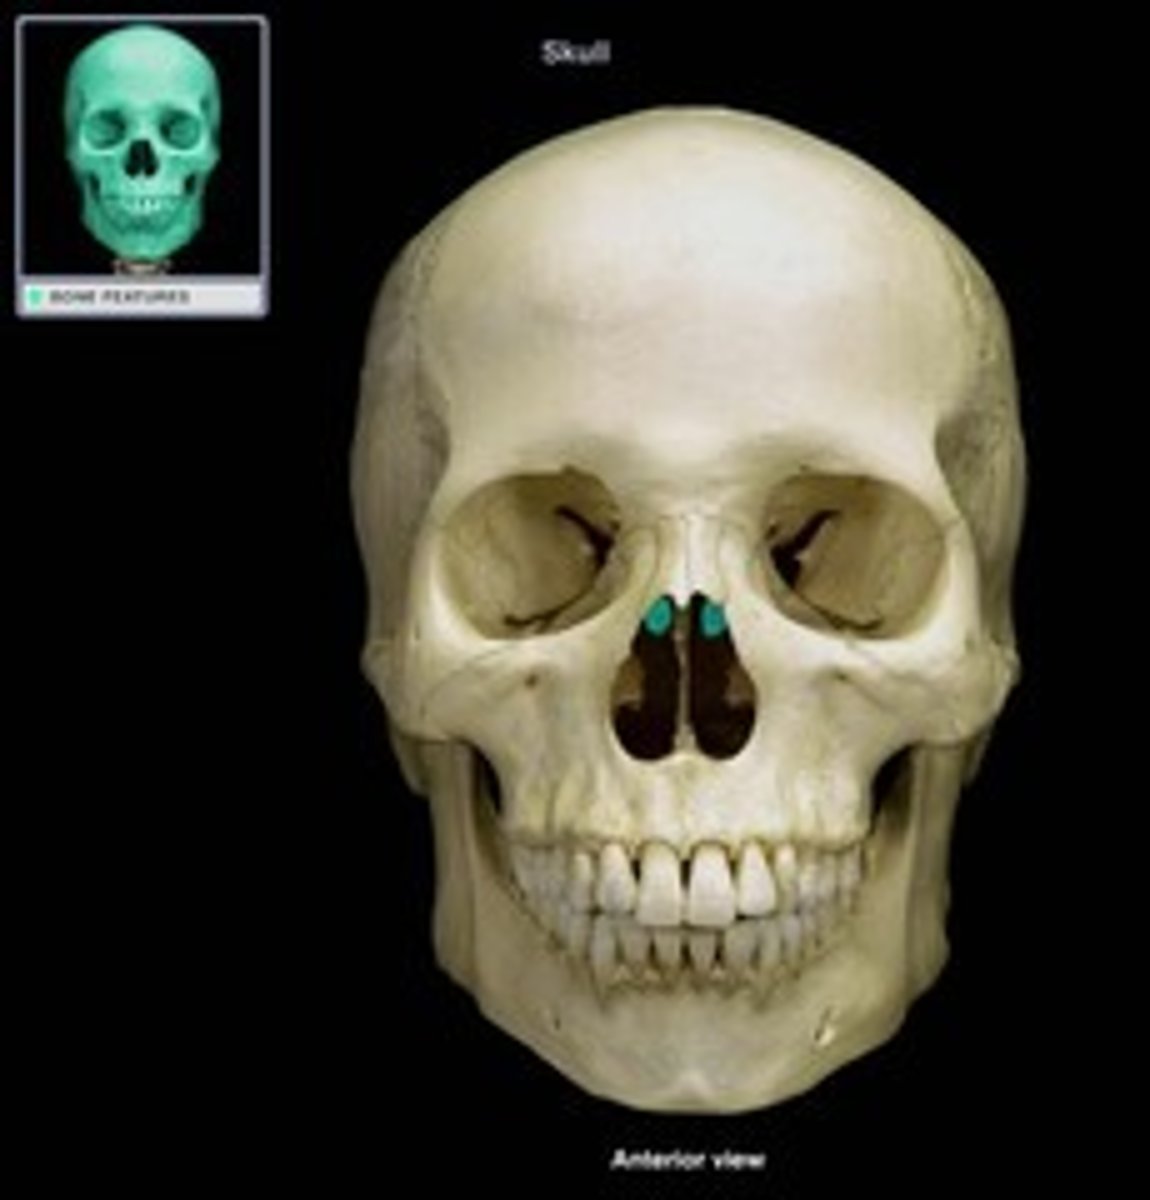

Perpendicular Plate of Ethmoid Bone

Cristi Galli

Cribriform plate of ethmoid

Superior and Middle Nasal Conch

Vomer

Inferior Nasal Concha